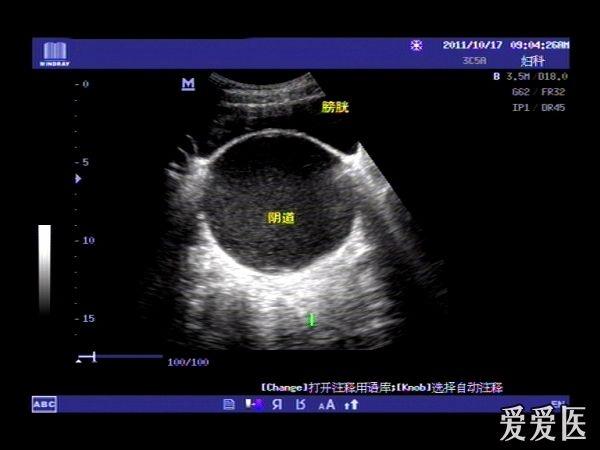

患者,女,14岁,因周期性下腹部胀痛不适3月余来我院就诊。查体:下腹部可扪及一包块。超声检查膀胱适度充盈,子宫前倾位,宫底部上移至脐平面,宫体宫腔,宫颈及**明显扩张呈椭圆形,内回声不纯净,呈细密的点状回声,宫内膜显示清晰。超声诊断处女膜闭锁